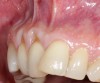

Fig 9. Two years postoperative. A complete root coverage and increase of the zone of attached and keratinized tissue is observed.

Figure 9

Fig 10. Cross-sectional view of the preoperative and postoperative (2 years). A three-dimensional increase of zone of keratinized and attached tissue is observed, restoring the lost attachment apparatus and correcting the gingival deformity in height and width.

Figure 10

Fig 11. Cross-sectional view of the preoperative and postoperative (2 years). A three-dimensional increase of zone of keratinized and attached tissue is observed, restoring the lost attachment apparatus and correcting the gingival deformity in height and width.

FIgure 11